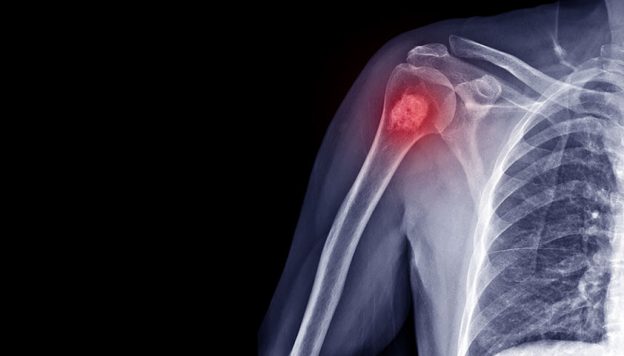

When a tumor develops in the body, some cells can break away and enter the bloodstream. These are called circulating tumor cells. Their presence can indicate a malignant process, even in early stages, before the tumor is visible on imaging tests (CT, MRI, ultrasound).